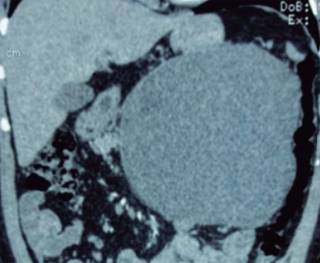

Paciente de 45 años con dolor abdominal generalizado, estreñimiento y náusea posterior a la alimentación. La radiografía de abdomen evidencia en el epigastrio imagen redondeada homogénea de mayor densidad, que desplaza las asas intestinales y el estómago. La tomografía muestra una imagen ovoidea de 20.8 centímetros de eje mayor (Figuras 1 y 2), con bordes lisos, septos delgados internos y densidades líquidas, proveniente de la raíz del mesenterio, sin conexión con otra estructura, con desplazamiento de las asas y el riñón derecho (Figuras 3 y 4).

Figura 2: Imagen simple de tomografía computada. Reconstrucción coronal abdominal donde se observa la lesión ya descrita.

El diagnóstico por imagen y confirmación patológica fue de quiste mesentérico gigante.